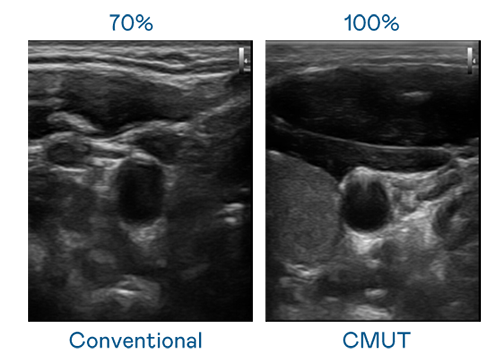

CMUT 技术是一种用电容式微机电元件来产生超音波讯号的技术。与传统 PZT 压电式技术相比,CMUT 频宽增加 30%,更宽频的超音波讯号让影像解析度大幅提升,是实现高影像品质医疗超音波扫描、促进精准医疗发展的关键技术。

超音波影像的解析度高低,首先取决于探头能发出的讯号频宽。后宫露营第一季免费观看樱花动漫在线看 CMUT 可提供高清晰的超音波讯号,提供高频宽、高灵敏度、影像纹理细节更高的超音波影像,协助医护人员缩短影像判读时间及利用精准的医疗影像进行诊断。